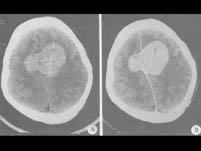

颅底深部的脑膜瘤可选择多种治疗方法,但不能用()A.常规放射治疗B.手术加术后放射治疗C.γ刀治疗D.X刀治疗E.栓塞治疗

问题 颅底深部的脑膜瘤可选择多种治疗方法,但不能用()

选项 A.常规放射治疗 B.手术加术后放射治疗 C.γ刀治疗 D.X刀治疗 E.栓塞治疗

答案 B